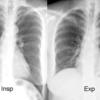

Insp & Exp

Ex 1

Date: 03/24/2004

Views: 5602